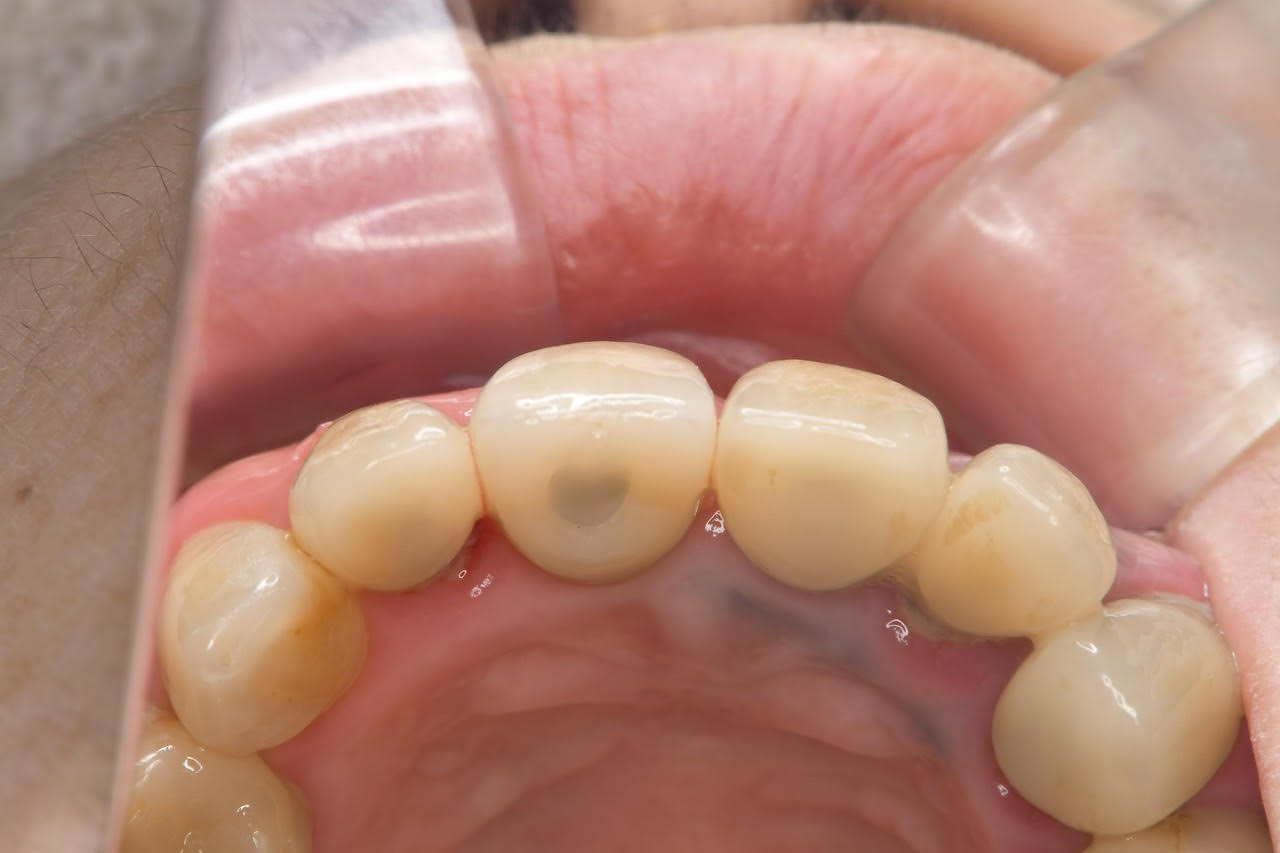

術後3ヶ月の治癒期間を経て、インプラントと骨が強固に結合していることを確認しました。

その後、最終的な上部構造(セラミックの被せ物)の型取りを行い、装着いたしました。

完成した前歯は、天然の歯と見分けがつかないほど自然な仕上がりとなりました。